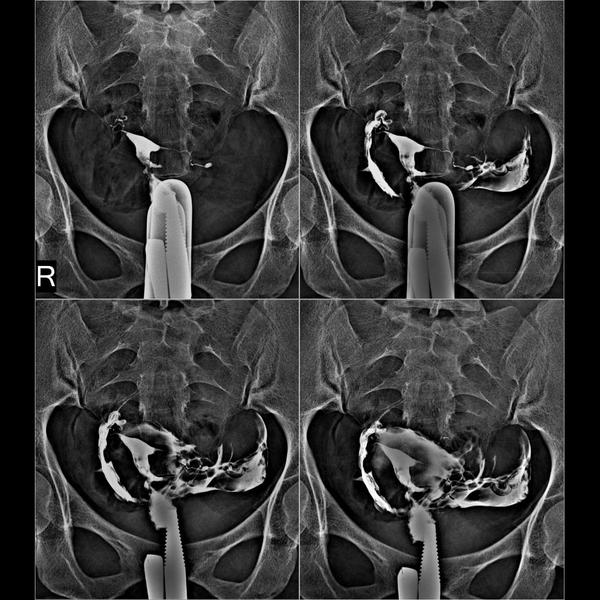

HSG (hysterosalpinogram)

HSG Test in pitampura. A hysterosalpingogram (HSG)...